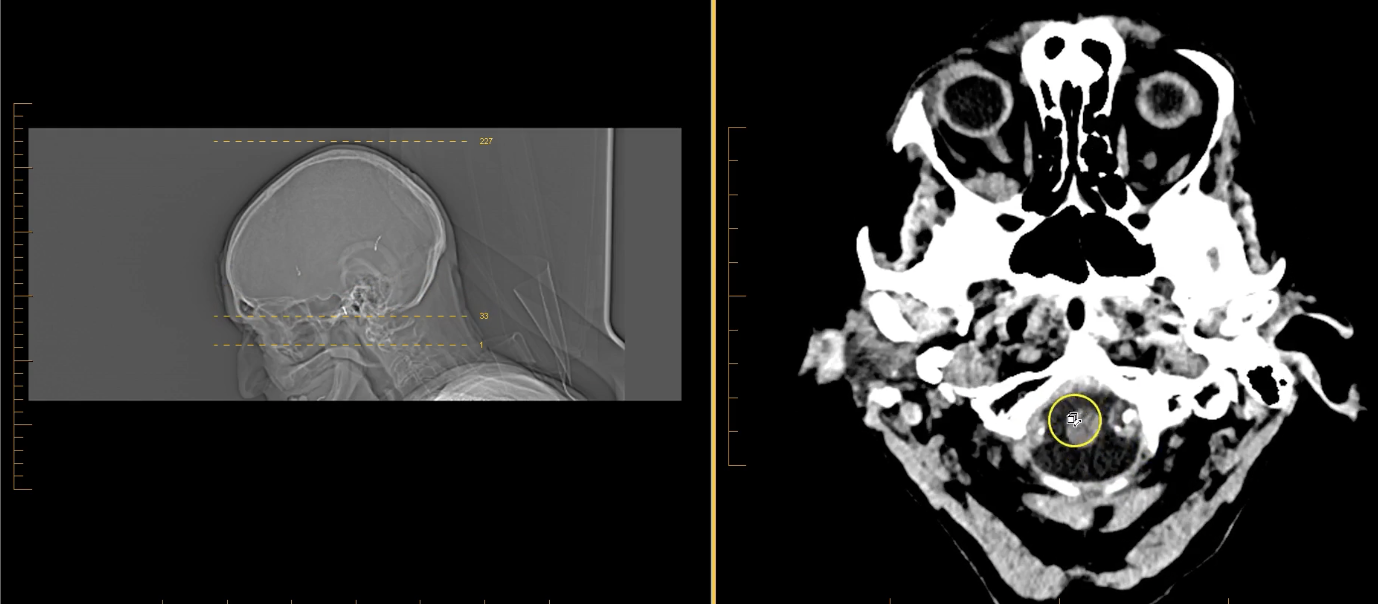

term image

pons